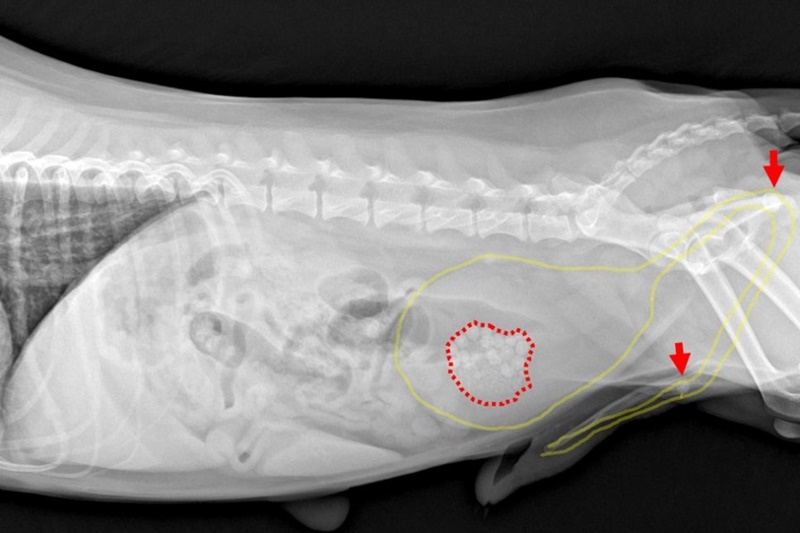

▲ 원인 평가를 위하여 혈액검사 진행 시 백혈구 수치 경도 상승 외에는 큰 특이사항 없었으나 엑스레이 상 요도 내에 결석 2개가 부분 폐색을 유발하고 있는 것이 확인됐습니다. 방광 내에서도 크기가 큰 결석이 다수 보였습니다.

검사 결과를 종합하였을 때 미우는 세균성 방광염이 동반된 방광/요도결석으로 진단됐습니다.